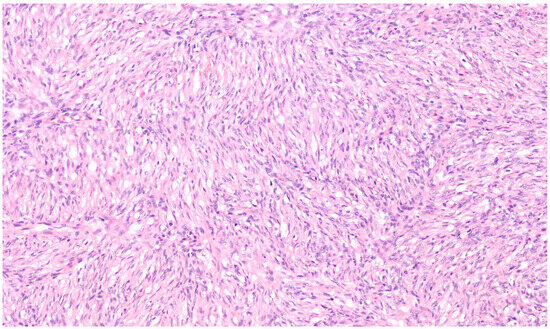

Microscopically, the majority of our cases had the typical aspect of DFSP, presenting as low to intermediate differentiated tumours composed of spindle cells embedded in a collagenous stroma; in 3/69 cases (4.3%), the stroma was described as myxoid. In DFSP, tumour cells are typically arranged in a storiform pattern and show the entrapment of subcutaneous adipose tissue with a sparing of adnexal structures (“honeycomb” pattern). The cytoplasm is scant, eosinophilic, and fibrillary; the nuclei have low-grade atypia and low mitotic activity (Figure 2 and Figure 3). The presence of higher nuclear pleomorphism and increased mitotic count indicates the presence of fibrosarcomatous transformation (DFSP-FS) and was reported in 9/69 cases (13%) [11].

Figure 3. Spindle cells have elongated and mildly hyperchromatic nuclei and are arranged in a storiform pattern, generally around small vessels (Haematoxylin–Eosin; 200×).